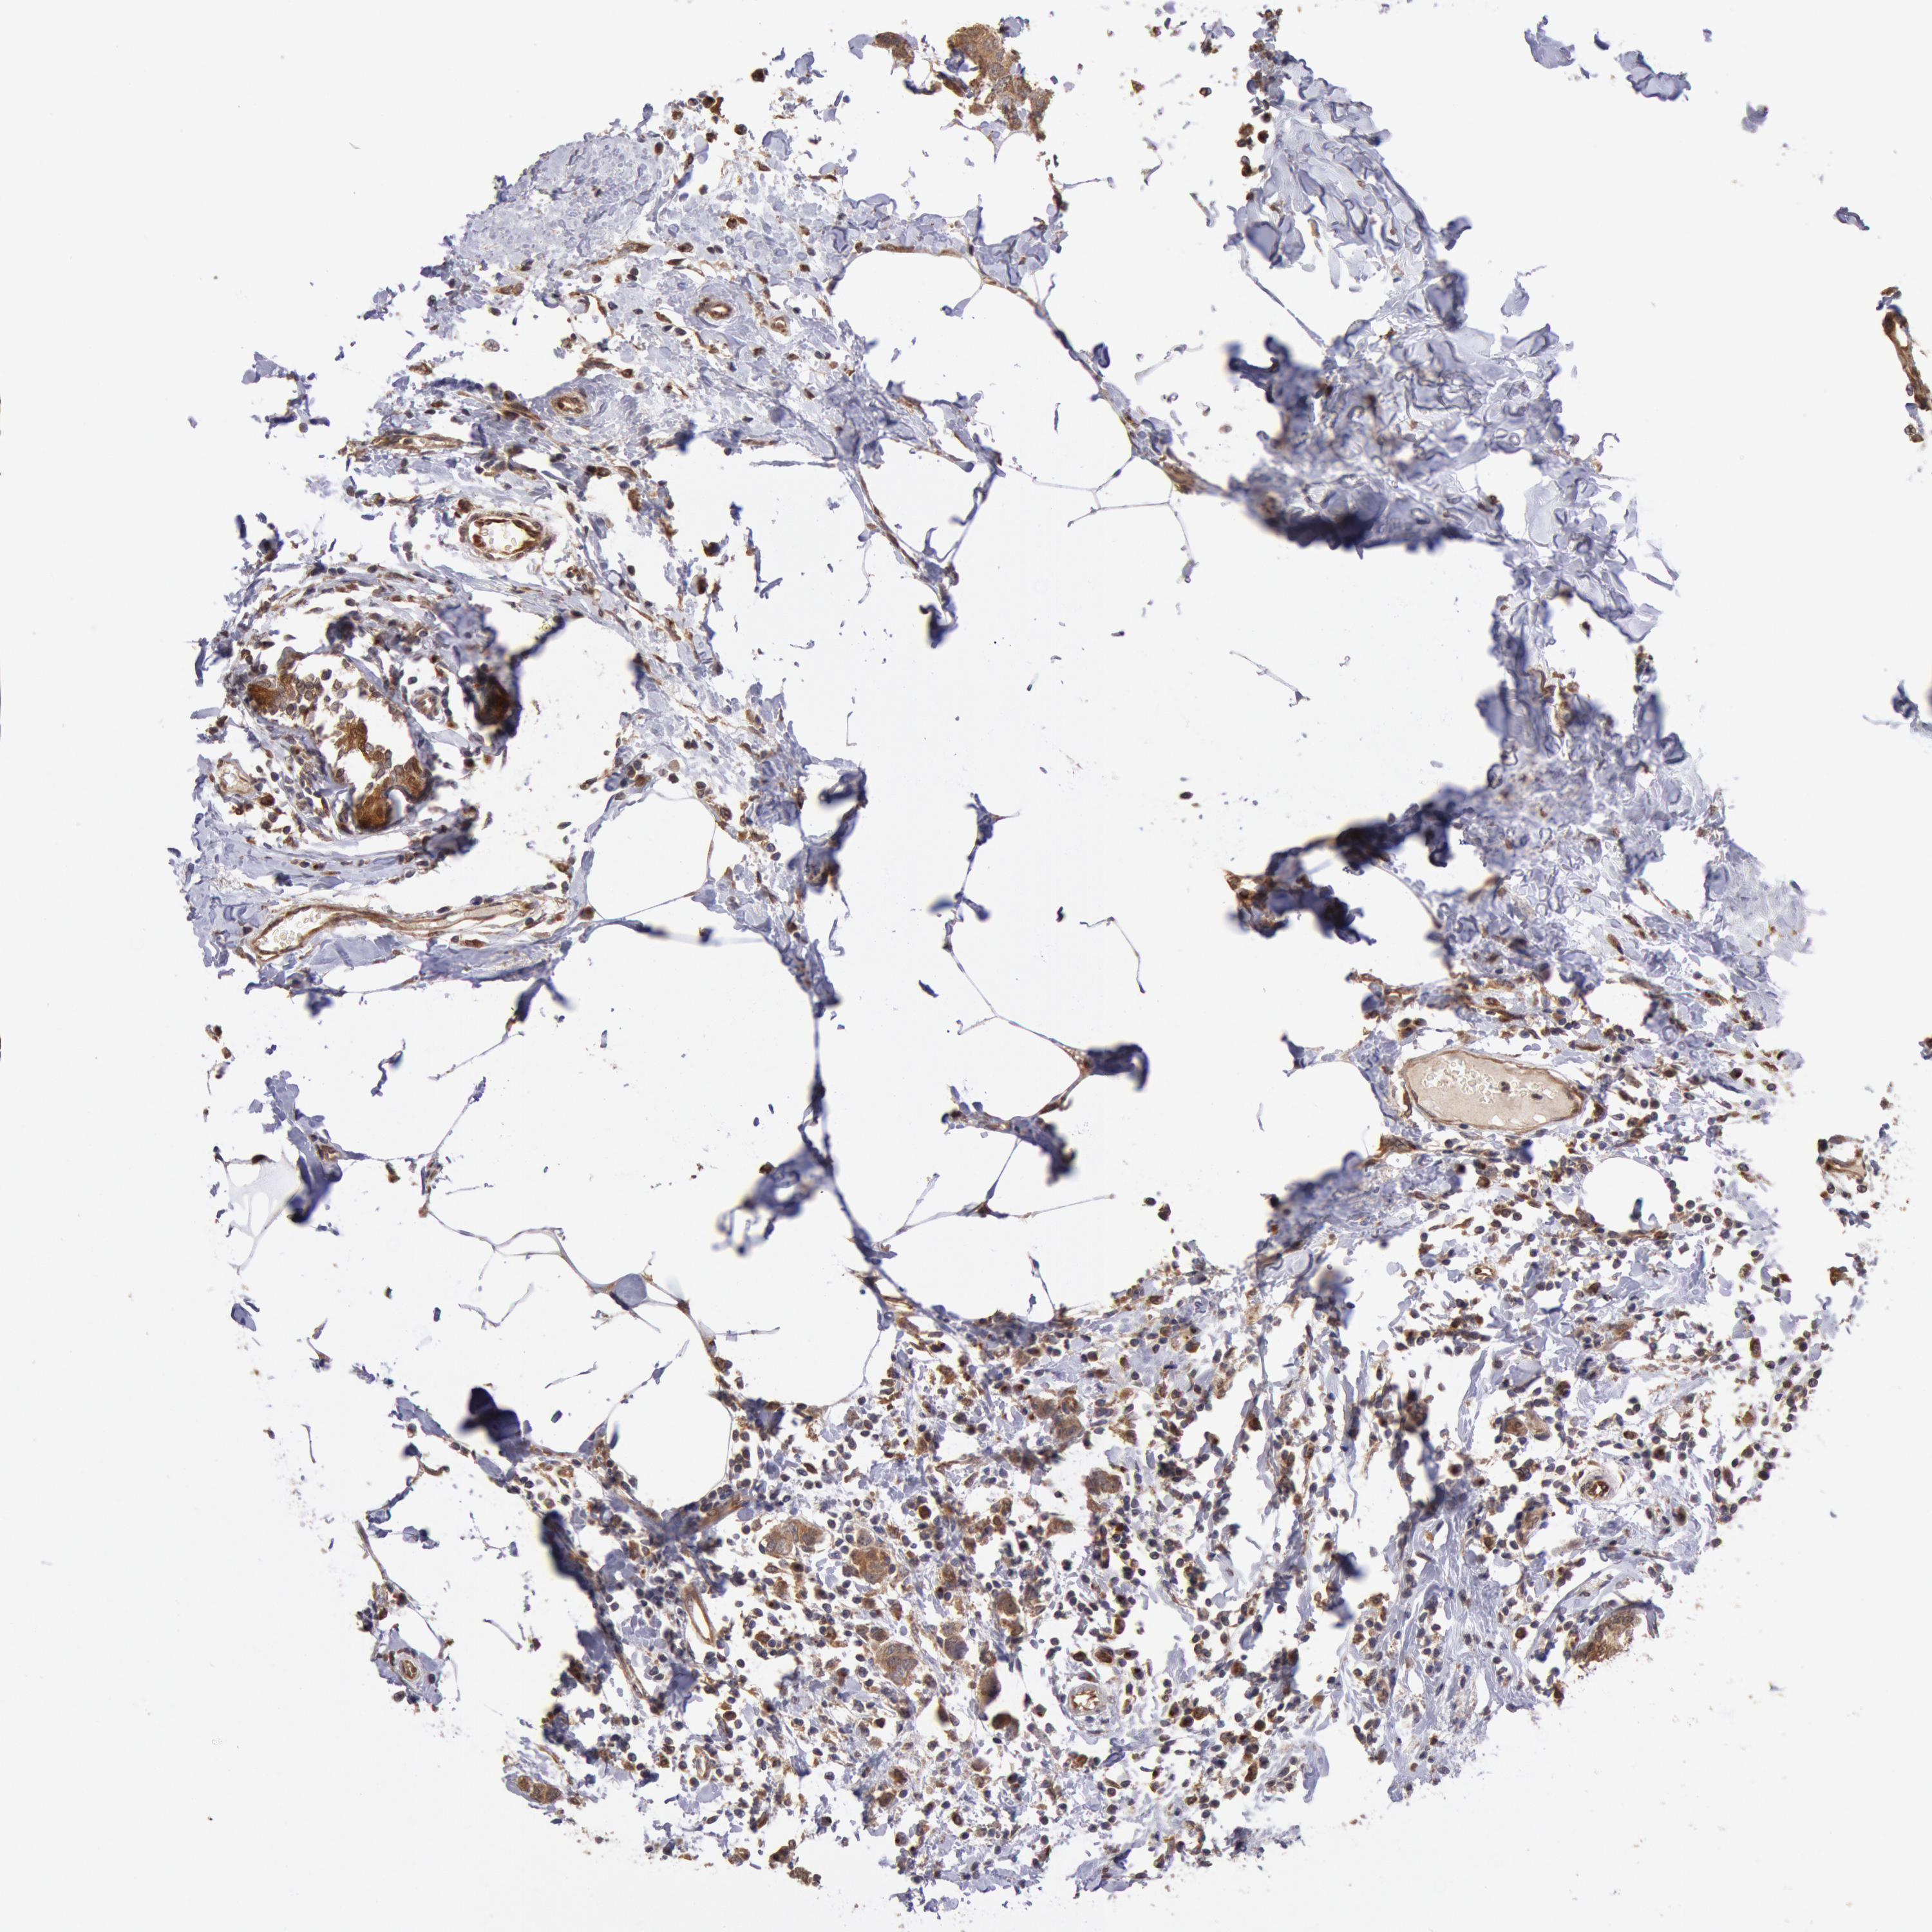

CANCER BREAST CANCER Show tissue menu

BRCA TCGA BRCA VALIDATION PROTEIN EXPRESSION

ANTIBODIES

AND

VALIDATION